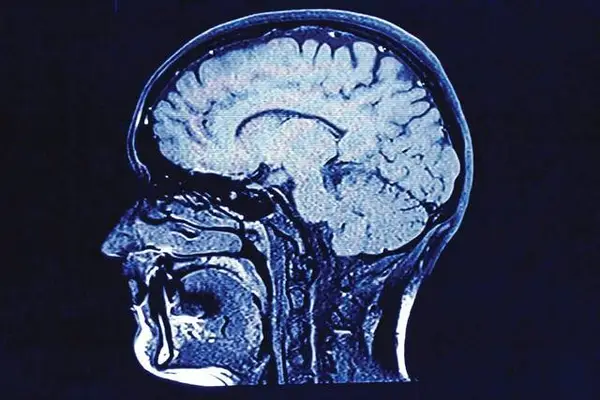

The largest study of its kind from the Boston University CTE Center reveals that the progressive brain disease chronic traumatic encephalopathy should be recognized as a new cause of dementia. Those with advanced CTE — who had been exposed to repetitive head impacts — had four times higher odds of having dementia.